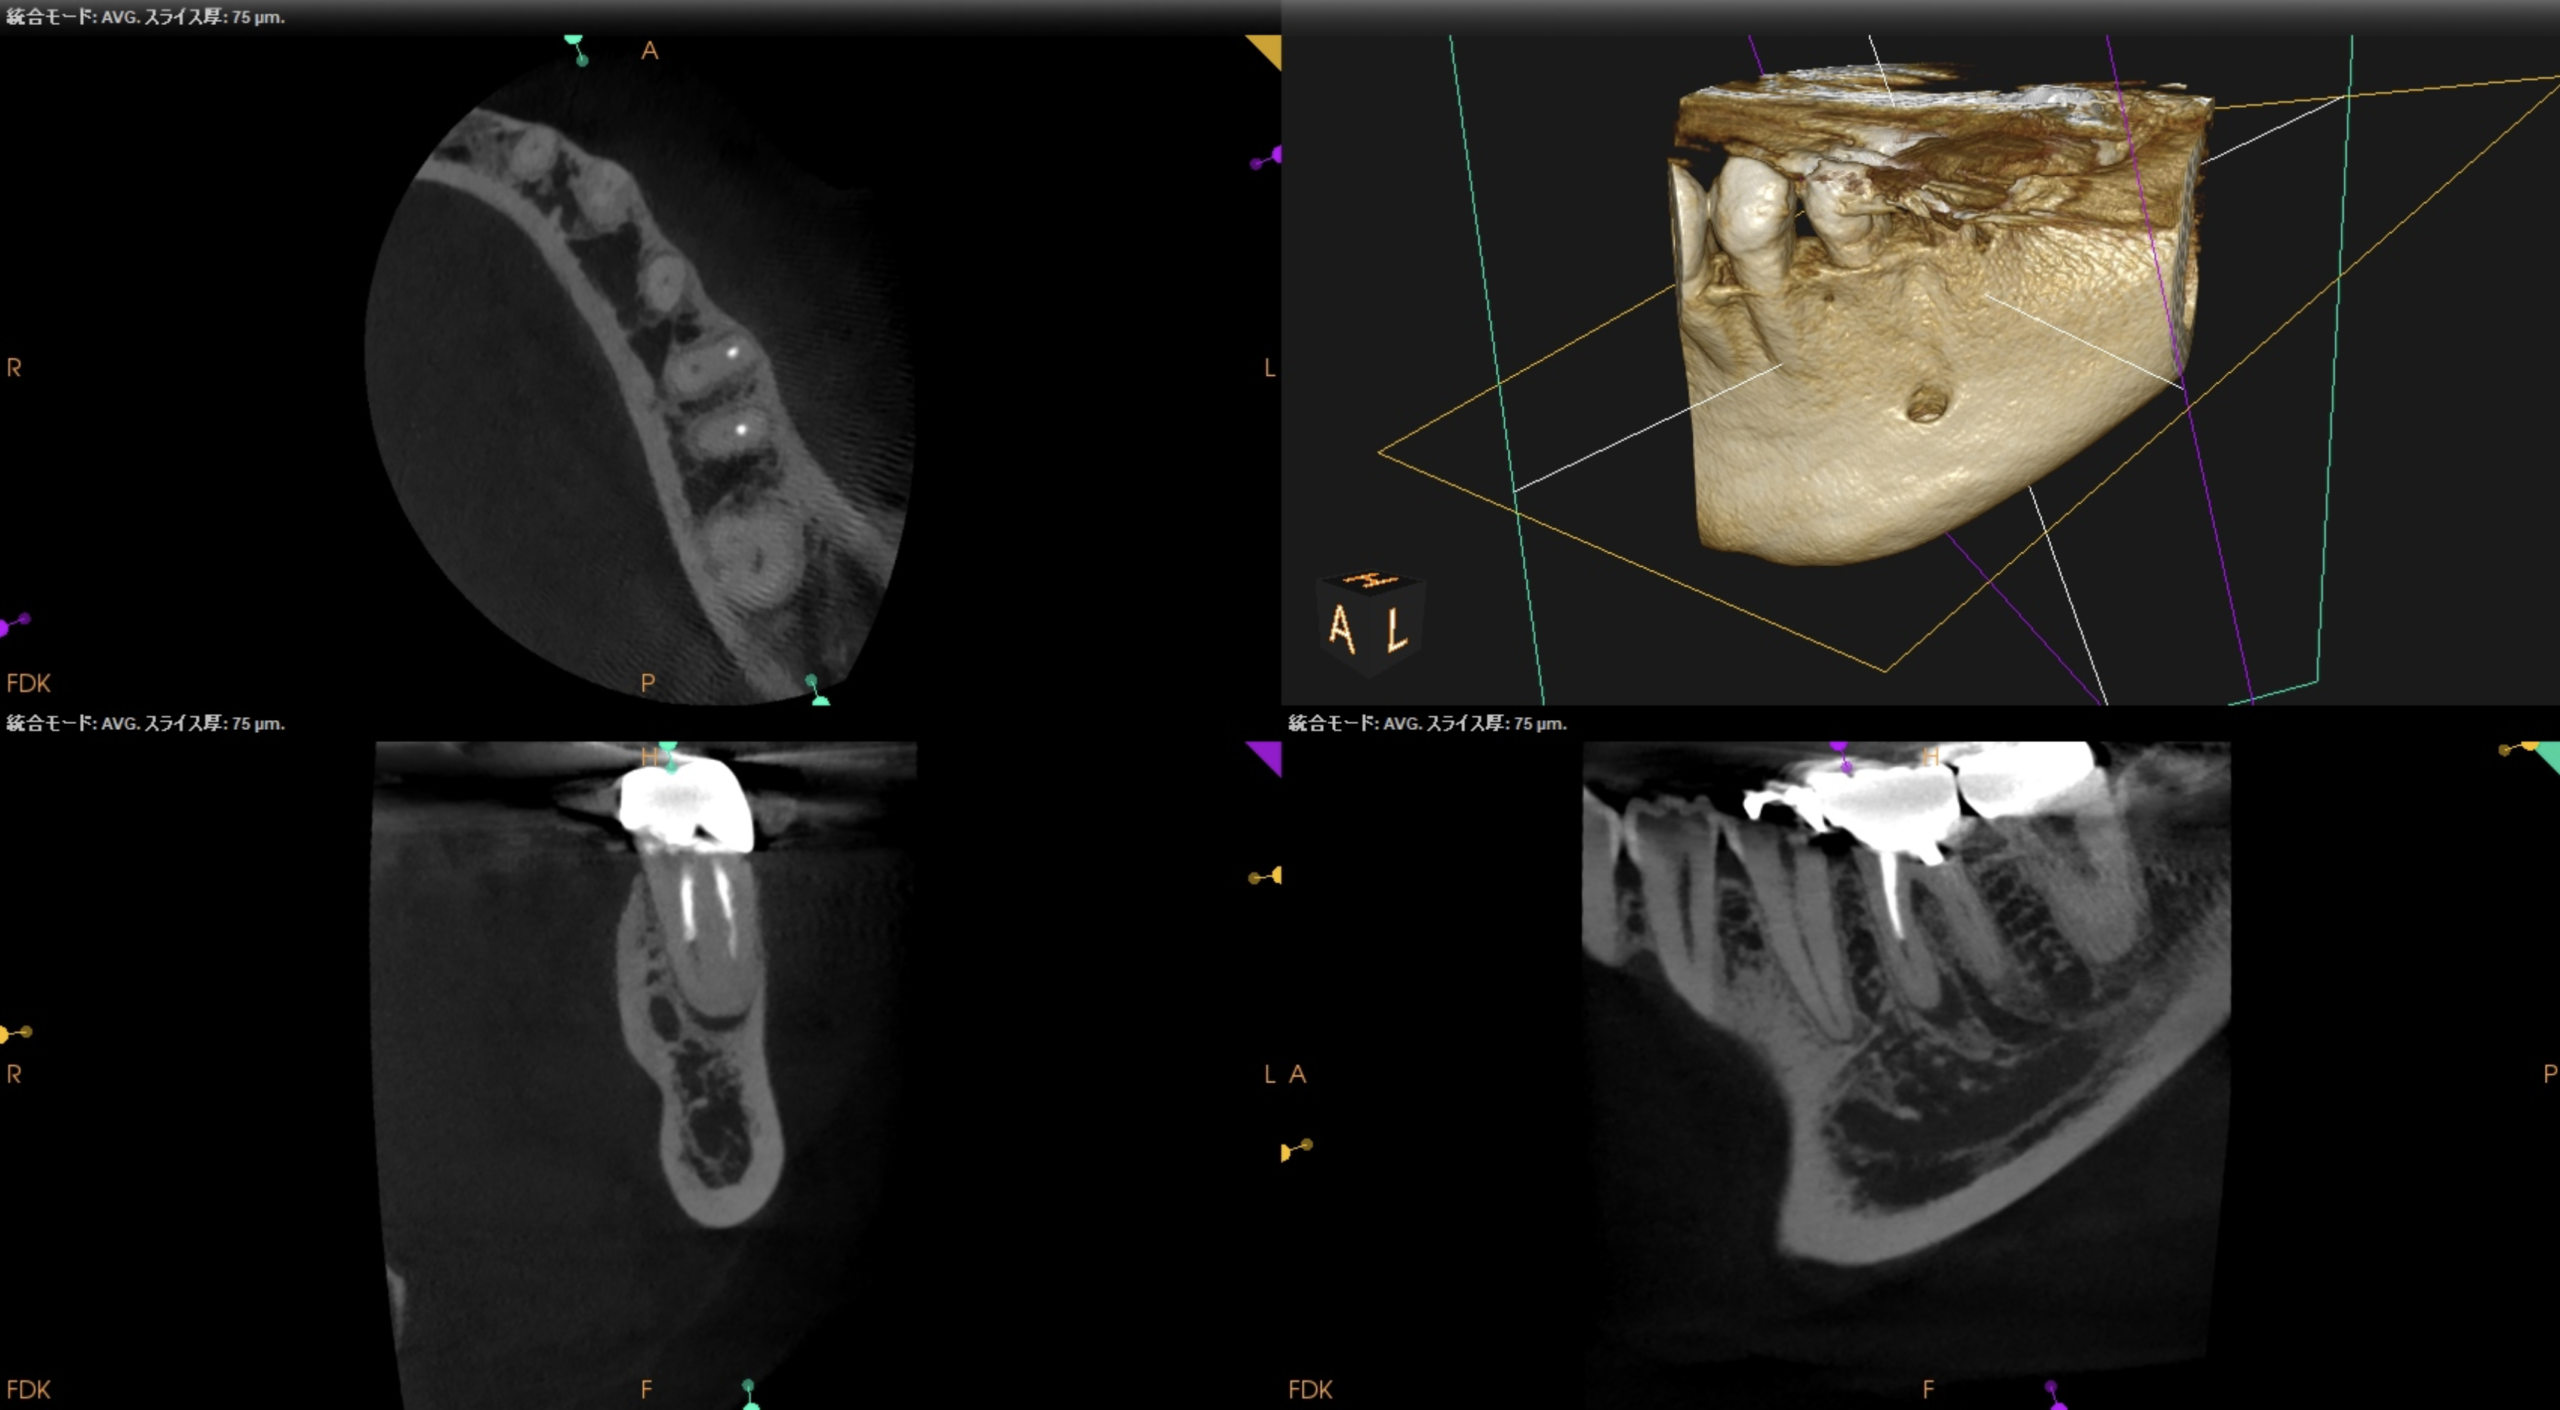

ということで臨在歯の#18もCBCTを精査した。

#18

M

D

#18 Mのこの絵は縁下カリエスの可能性を示唆している。